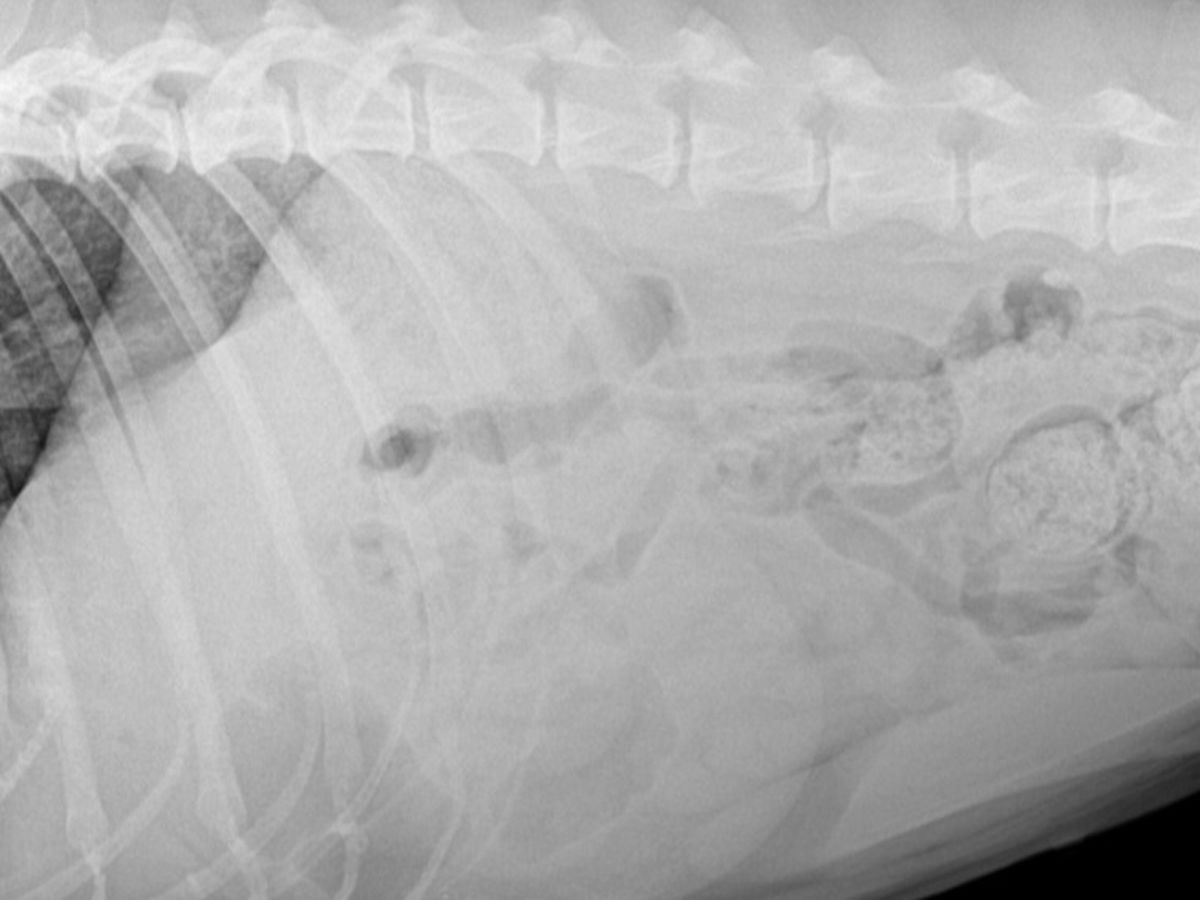

This fundraiser is to help Dori get the medical she needs. She started off with a bladderstone the size of a tangerine . She had emergency surgery and had it removed. She is now having incontinence and severe pain when she urinates. She has had xrays and an ultrasound that has given us no answers besides the fact that her liver is inflamed and her lungs are congested. We have been referred to an internal medicine doctor to do more test. This poor girl is uncomfortable and has no answers or relief. We will not give up on her and continue to do whatever it takes to get answers. Please help us help her. She is an amazing dog who has been delt an awful hand in life.